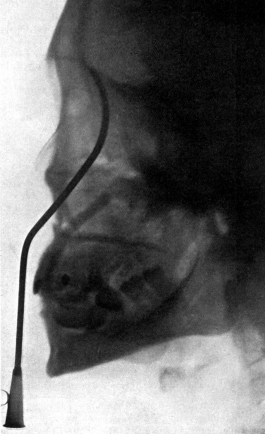

| 210. | Passing the Eustachian Catheter | 365 |

| 211. | Passing the Eustachian Catheter | 365 |

| 212. | Passing the Eustachian Catheter | 366 |

| 213. | Passing the Eustachian Catheter | 366 |